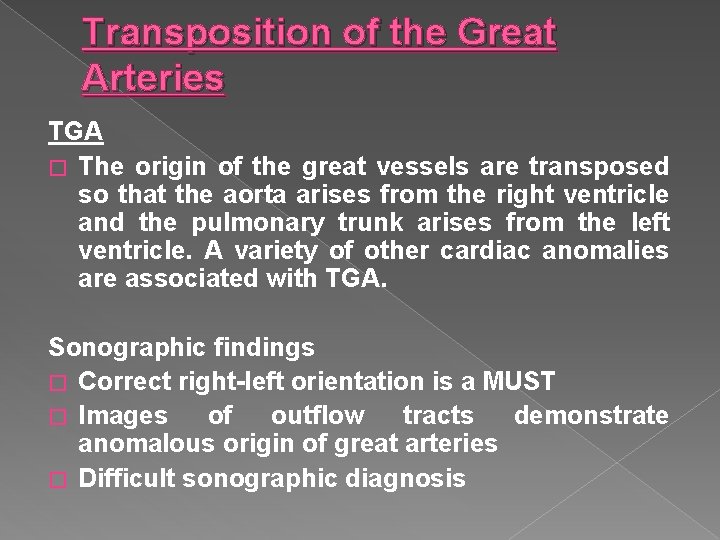

Transposition of the Great Arteries TGA � The origin of the great vessels are transposed so that the aorta arises from the right ventricle and the pulmonary trunk arises from the left ventricle. A variety of other cardiac anomalies are associated with TGA. Sonographic findings � Correct right-left orientation is a MUST � Images of outflow tracts demonstrate anomalous origin of great arteries � Difficult sonographic diagnosis